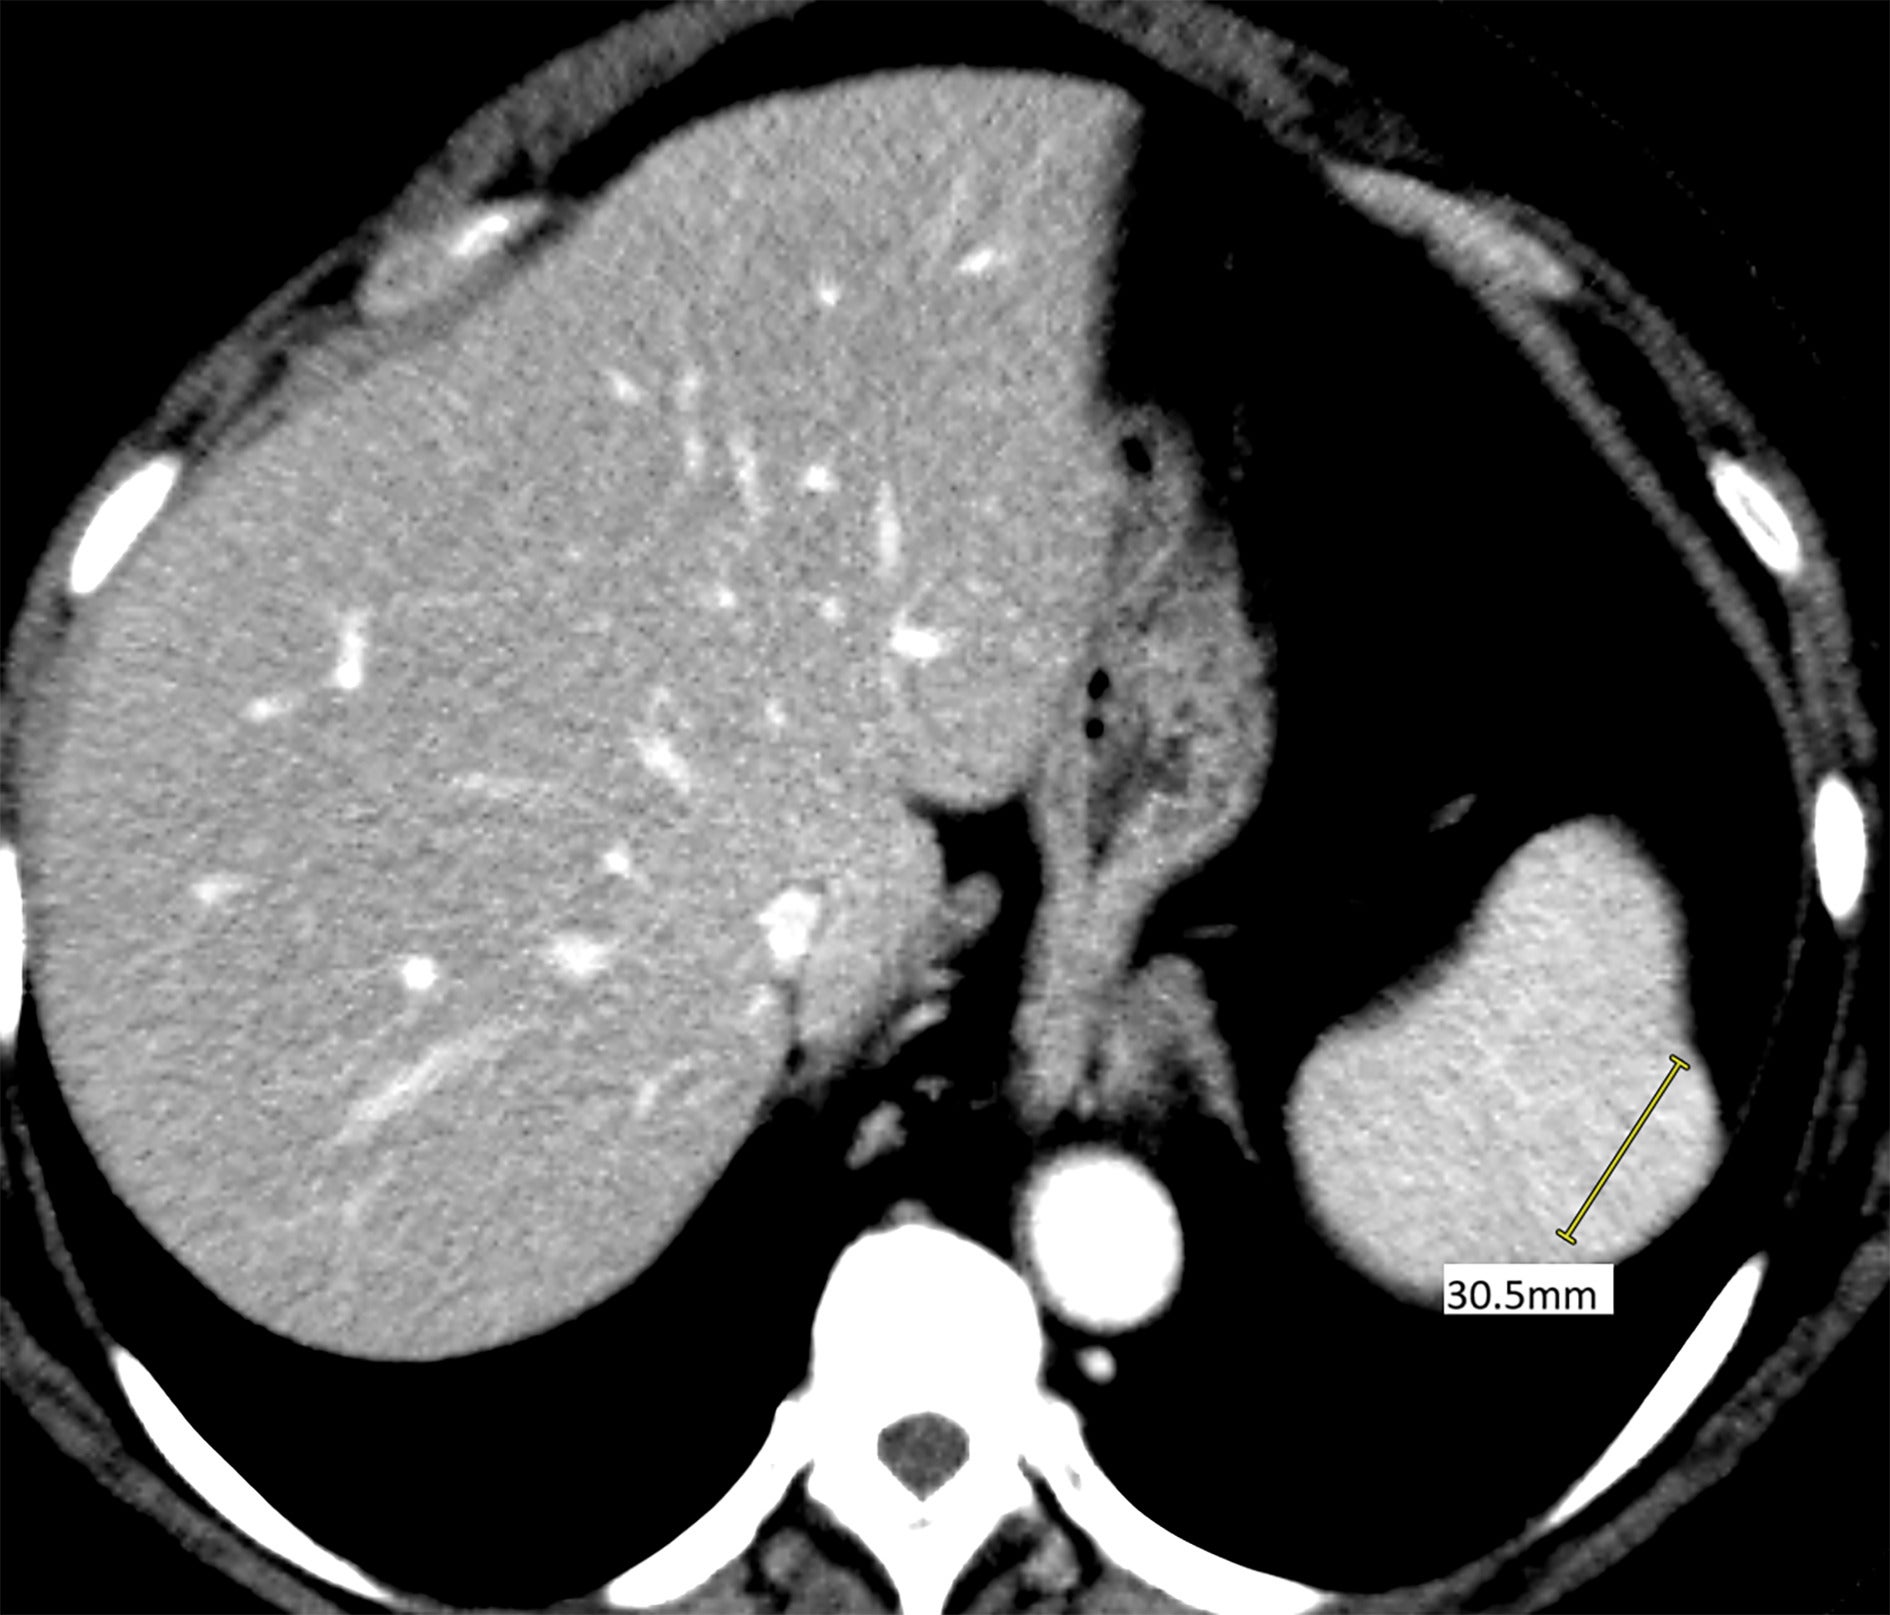

Given the patient’s cancer history and anemia, CT imaging was performed, demonstrating a mildly hyperdense 13.1 cm lesion in the portal venous phase ( Figure 1 ), with no other significant findings. Multiphasic, multiplanar MRI demonstrated a 3.3 cm × 2.7 cm mildly T2 hyperintense, enhancing lesion in the posterior aspect of the spleen ( Figure 2 ).

Axial CT abdomen demonstrates a mildly hyperdense solitary 3.1 cm lesion in portal venous phase.